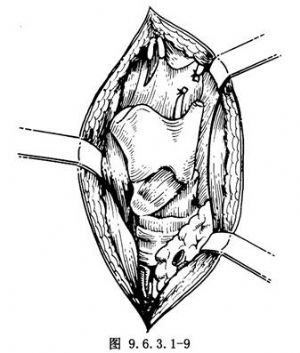

(4)鬆動喉體:先於甲狀舌骨膜兩外側甲狀軟骨上角上方,分出喉上動、靜脈並結紮切斷(圖9.6.3.1-9),同時切斷喉上神經,用骨剪剪斷甲狀軟骨上角,沿甲狀軟骨翼板後緣切斷嚥下縮肌(圖9.6.3.1-10)。此時應注意結紮甲狀腺上動脈的環甲支,然後將梨狀窩黏膜自甲狀軟骨翼板後內側面分離。再沿甲狀軟骨板後下緣向下切斷甲狀軟骨下角。